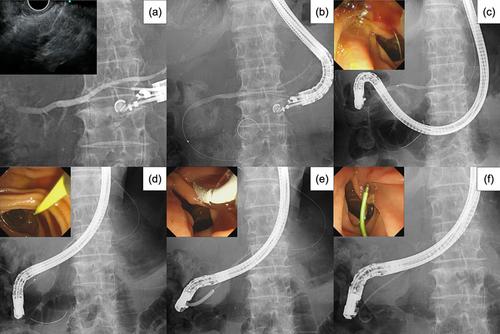

Mukai and colleagues describe endoscopic ultrasound-guided rendezvous using a 22-gauge needle and stiff 0.018-inch guidewire, enabling pancreatic duct stenting without guidewire exchange or tract dilation. This streamlined approach enhances flexibility, reduces invasiveness and risk, and lowers cost, supporting its potential as a first-line method in challenging transpapillary cases.